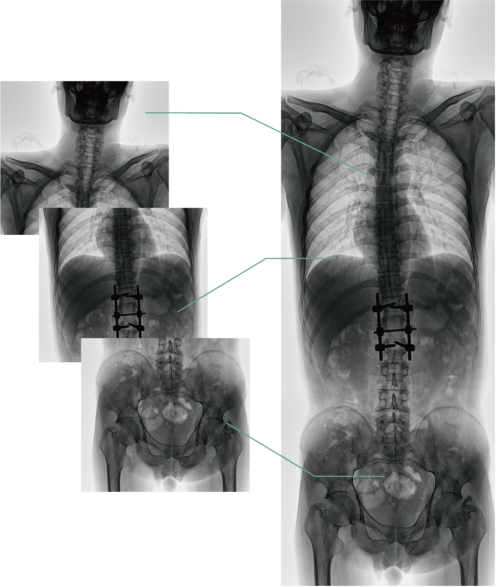

四、圖像自動(dòng)拼接

圖像自動(dòng)拼接功能實(shí)現(xiàn)全脊柱、全下肢全景攝影,解決在觀察頸椎至尾椎的脊柱側(cè)彎或其他病變時(shí)不能一次成像的問題,能夠直觀的顯示脊柱和下肢的整體解剖形態(tài)及側(cè)凸部位。